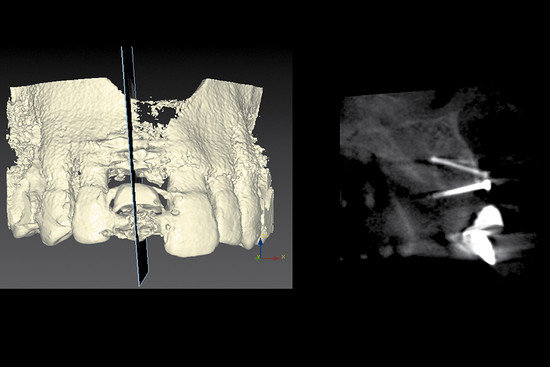

Zdjęcie CBCT ukazujące objętość kości przed implantacją. Kość została uzupełniona autologicznym bloczkiem kostnym. Jednak w skutek resorpcji kości, miejsce te potrzebuje dodatkowej augmentacji w czasie wstawienia implantu.

Widok w trakcie operacji na implant wstawiony w odbudowaną kość, która wymaga modelowania, aby poprawić efekt estetyczny w obrębie zęba 11.

Wypełnienie grzbietu małymi granulkami Geistlich Bio-Oss®, który pokryty jest Geistlich Bio-Gide® Compressed, aby poprawić kontur tkanki twardej oraz efekt estetyczny.